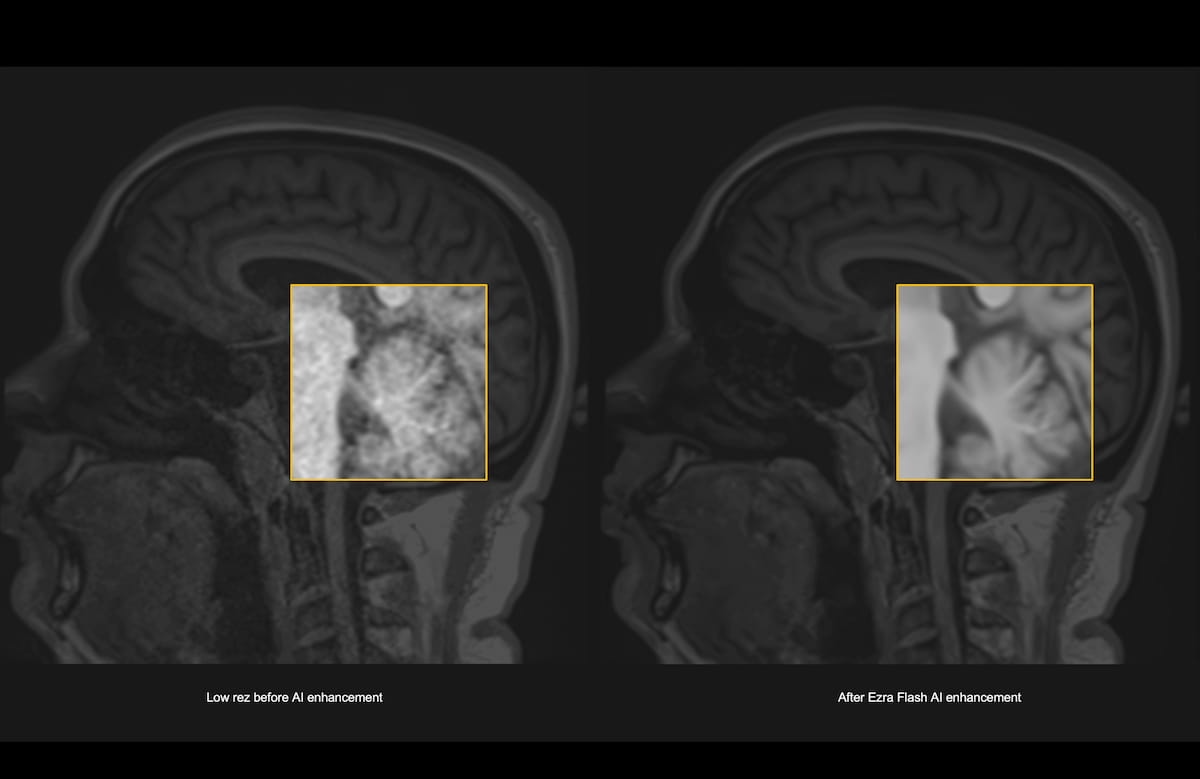

Conditional use of full-body magnetic resonance imaging (MRI) is reportedly permitted for patients using any of the models for the remede® System, an implantable nerve stimulation therapy indicated for the treatment of adults with moderate to severe central sleep apnea.